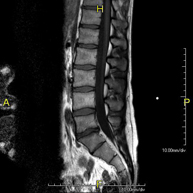

- RM Columna lumbar

Prueba diagnóstica no invasiva que consiste en la obtención de imágenes de alta definición anatómica de la lumbar y sacra, mediante el empleo de un campo electromagnético y ondas de radio (con un emisor y un receptor). No utiliza radiación ionizante. Indicaciones: traumatismos, ciática, hernias discales, tumores, infecciones.

Prueba diagnóstica no invasiva que consiste en la obtención de imágenes de alta definición anatómica de la lumbar y sacra mediante el empleo de un campo electromagnético y ondas de radio (con un emisor y un receptor). No utiliza radiación ionizante. Indicaciones: traumatismos, ciática, hernias discales, tumores, infecciones.